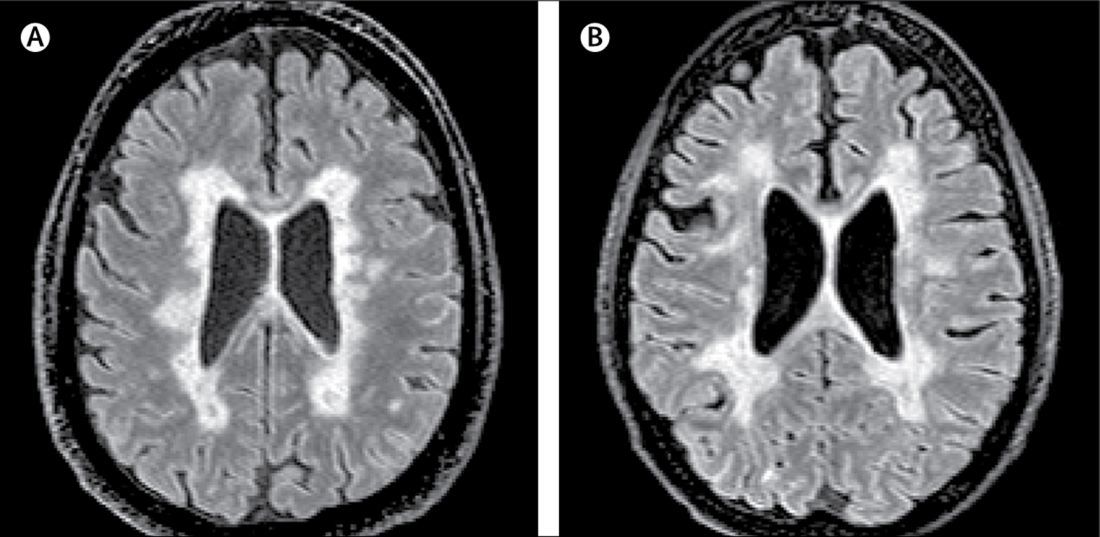

What are the typical diagnostic features seen with an MRI of the head and CT of the spine in a patient with MS?